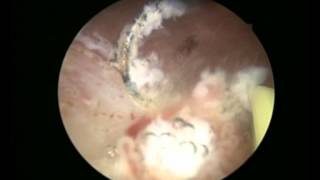

Μέθοδο TURis

Video Gallery